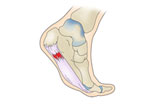

Á·Àú±Ù¸·¿°

¾ÆÅ³·¹½º°Ç¿°

Æò¹ß